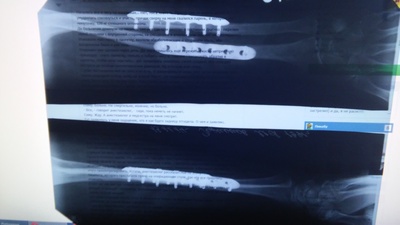

Автор поста оценил этот комментарий

Ооо, братан, тоже самое. Почти год прошел. На рентгене как у тебя, только ближе к кисти. Тоже с велика упал. До сих пор не могу восстановить движение вокруг оси кисти. Как думаешь, пластину снимать надо будет?

Иллюстрация к комментарию